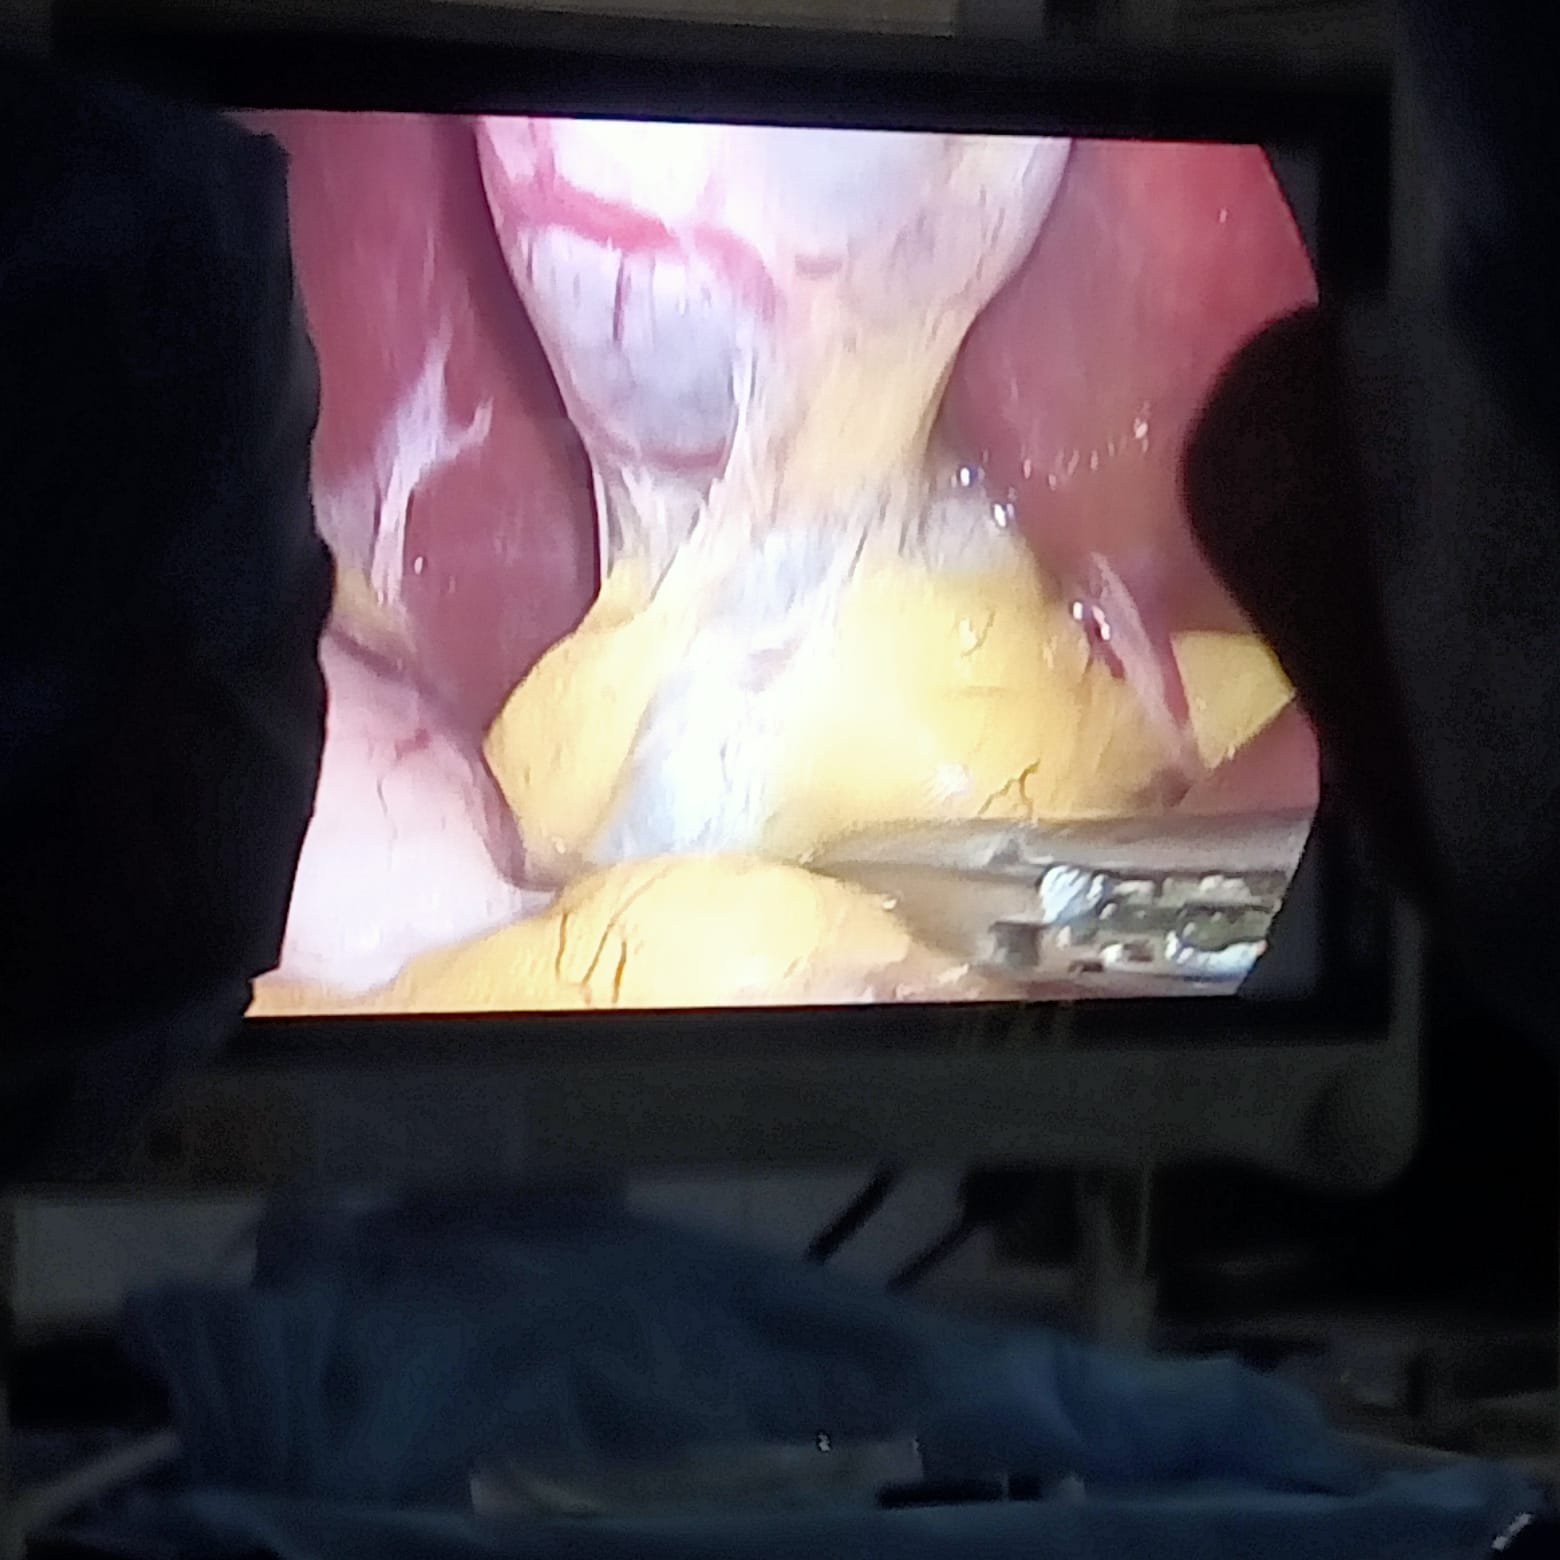

Laparoscopic Surgery

Minimally invasive laparoscopic surgery uses small incisions and a camera to perform operations. This means less pain, smaller scars, shorter hospital stays, and faster return to daily activities.